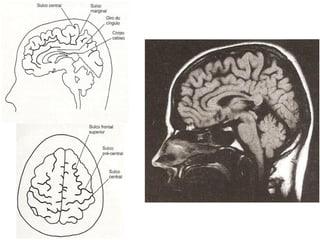

Ressonância Magnética do Crânio

• Sistema de obtenção de

imagens é mais sensível à

natureza molecular dos tecidos;

• Alta densidade tissular não

resulta em resolução de

contraste.

   Doenças da substância branca;

   Neoplasias;

   Doenças infecciosas;

   Distúrbios hemorrágicos;

   Distúrbios isquêmicos.

Tálamo

Hipotálamo

Hipófise

4º ventrículo

Sulco       Sulco

pré-central   central